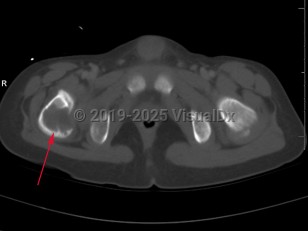

Eosinophilic granuloma of bone in Child

Langerhans cell histiocytosis (LCH) refers to a spectrum of diseases that includes eosinophilic granuloma (EG), Hand-Schuller-Christian disease, and Letterer-Siwe disease. EG is a rare (seen in 1-5 per million), benign tumor-like disorder that features clonal proliferation of Langerhans cells (antigen-presenting mononuclear cells of dendritic origin) usually found in bones; however, this can involve other organ systems. EG occurs most often in children aged 5-15 years, with a male-to-female ratio of 2:1. EG constitutes 60%-80% of cases of LCH and accounts for less than 1% of all bone tumors. Ninety percent of cases involve a single lesion, usually in the axial skeleton, with just under 10% of cases involving lesions in multiple bones or lesions in other organ systems (ie, skin, pituitary gland, gastrointestinal [GI] tract, lung, spleen, or brain).

The clinical presentation of EG depends largely on the location affected. EG is most often confined to the axial skeleton. EGs are often asymptomatic and found incidentally, or may initially present with pain and swelling of the affected area, with or without decreased range of motion. Commonly affected areas of the skeleton include (in order of frequency): skull, femur, pelvis, mandible, clavicle, ribs, and long bones (of the diaphysis and metaphysis).